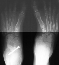

Radiographs reveal the following deformities:

- hindfoot valgus with AP talocalcaneal angle of > 35 degrees

- lateral subluxation/dislocation of the navicular from the talar head

- adduction of the metatarsals with the talus- 1st metatarsal angle to

be divergent medially

- increased lateral talocalcaneal angle with talus plantarflexed on calcaneus

RADIOGRAPHIC FEATURES:

- lateral displacement of the navicular on the head of the talus

-navicular ossification however does not occur until 1-2 yrs in females

and yrs in males

- metatarsal adduction

- line drawn through the long axis of the first metatarsal and line drawn

through the long axis of the talus should be parallel or divergent laterally

in the normal foot on AP radiograph

- widening of the talocalcaneal angle on AP radiograph- usually greater

than 35 degrees

- increased lateral talocalcaneal angle with planterflexion of the talus